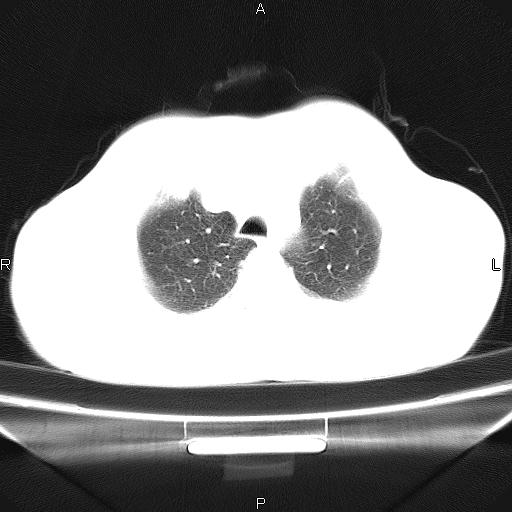

左下肺片状高密度影,境界模糊,密度不均,考虑感染性病变可能性大,建议抗炎治疗后复查。左肺门增大,不除外占位性病变,必要时支气管镜检。

考虑感染性病变可能性大,抗炎后复查,占位不排除。

建议强化或纤支镜观察,考虑肿瘤性病变可能性大

考虑感染性病变,不除外占位,建议抗炎后复查。